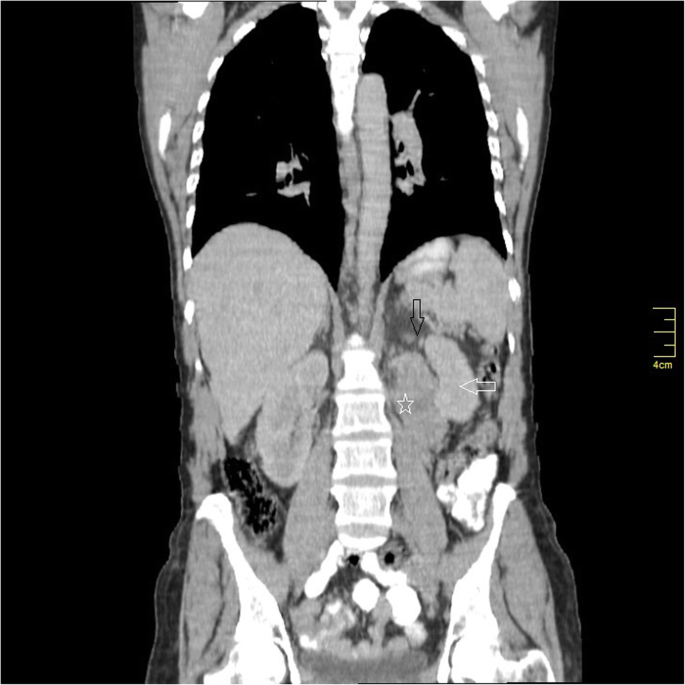

Computed tomography (C.T) with intravenous and oral contrast demonstrated a well defined heterogeneous retroperitoneal mass 9 × 7.3 × 6.5 cm containing a necrotic centre with well peripheral enhancement. The mass was located anteromedial to the left kidney and separated from the left adrenal gland, anterolateral to the aorta and connected with the 4th duodenal segment. No evidence of lymph node enlargement or metastatic lesion was noticed (Figs 1, 2, 3). These findings raised a differential diagnosis of duodenal GIST.

Preoperative assessment revealed controlled vital signs. During the induction of general anaesthesia and intubation, all vital signs remained normal. When midline incision was preformed, BP and pulse started shooting up (220\130–250\145) mmHg and (120–135) bpm respectively. To control hypertension, deepening the anaesthesia was performed by administration of sedative and analgesic drugs, in addition to vasodilator drugs. The decision was taken to perform minimal manipulation mass excision. At first, the mass appeared to be retroperitoneal adherent to the 4th segment of the duodenum and Treitz ligament with hypervascularized surface and strict adherence posteriorly (Fig. 4). The mass showed neovascularisation from the duodeno-jejunal junction with dense adhesion with the 4th segment of the duodenum without invasion (Fig. 5). Thereafter, the mass was found to be located paravertebral between the aorta and the left kidney and separated from the left kidney and the left adrenal gland. During careful dissection of the mass posteriorly of the aorta and the fatty tissue of the left kidney (Fig. 6), BP and pulse were around (180\110–240\135) mmHg and (130–145) bpm respectively. When the mass main draining vein was ligated, BP dropped dramatically to (50\30) mmHg, so high amounts of crystalloid and vasoconstrictive agents were applied. Due to the mass invasion, an injury of the left renal vein occurred and repair of the vein was carried out. 2000 ml of blood lost and six blood units were transfused. The patient was observed in intensive care unit for 24 h and her vital signs stayed stable. Postoperative course was uneventful. The patient was discharged home on postoperative day six. The histopathology study raised a suspicion of paraganglioma (Figs 7, 8). The immunohistochemical staining studies were positive for neuroendocrine markers chromogranin, synaptophysin, NSE and CD56 (Figs. 9, 10). S100 marker and CK were negative (Fig. 11) and Ki67 marker showed low mitotic index (Fig. 12). Lastly, the diagnosis of paraganglioma was confirmed. All medications were stopped. After 3 months, her follow up was normal. Written informed consent was obtained from the patient.